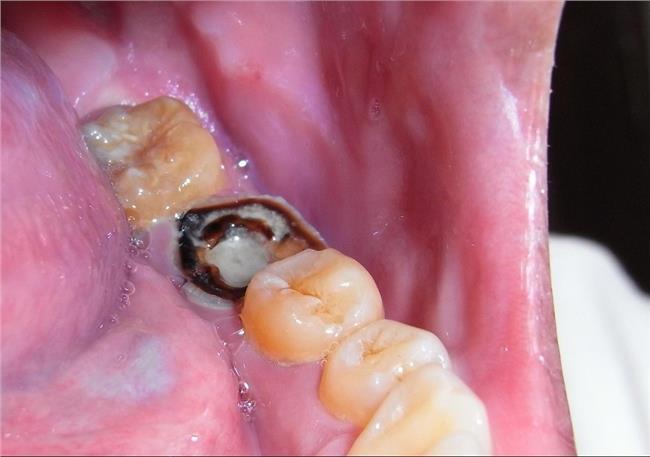

龋病

龋病是由于细菌的作用造成牙体硬组织脱矿和有机物分解,表现为牙体硬组织的变色、脱钙软化和龋洞形成,病变进一步发展可伴随牙髓充血、牙髓炎、牙髓坏死、根尖周炎、根尖周脓肿等。龋坏严重者,可造成牙冠部分或全部破坏,形成残冠、残根。